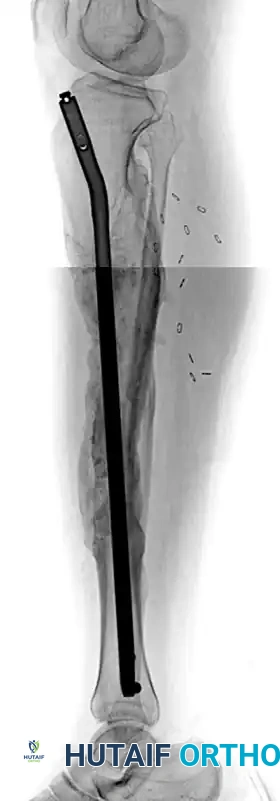

FIGURE 58-18: A, Deformity correction in the coronal plane utilizing the clamshell osteotomy technique. B, Sagittal plane correction demonstrating the restoration of the anatomical axis prior to intramedullary nailing.

FIGURE 58-19 (B): Lateral radiograph 1 year after surgery, showing complete osseous union and restoration of the sagittal mechanical axis following intramedullary nail fixation.